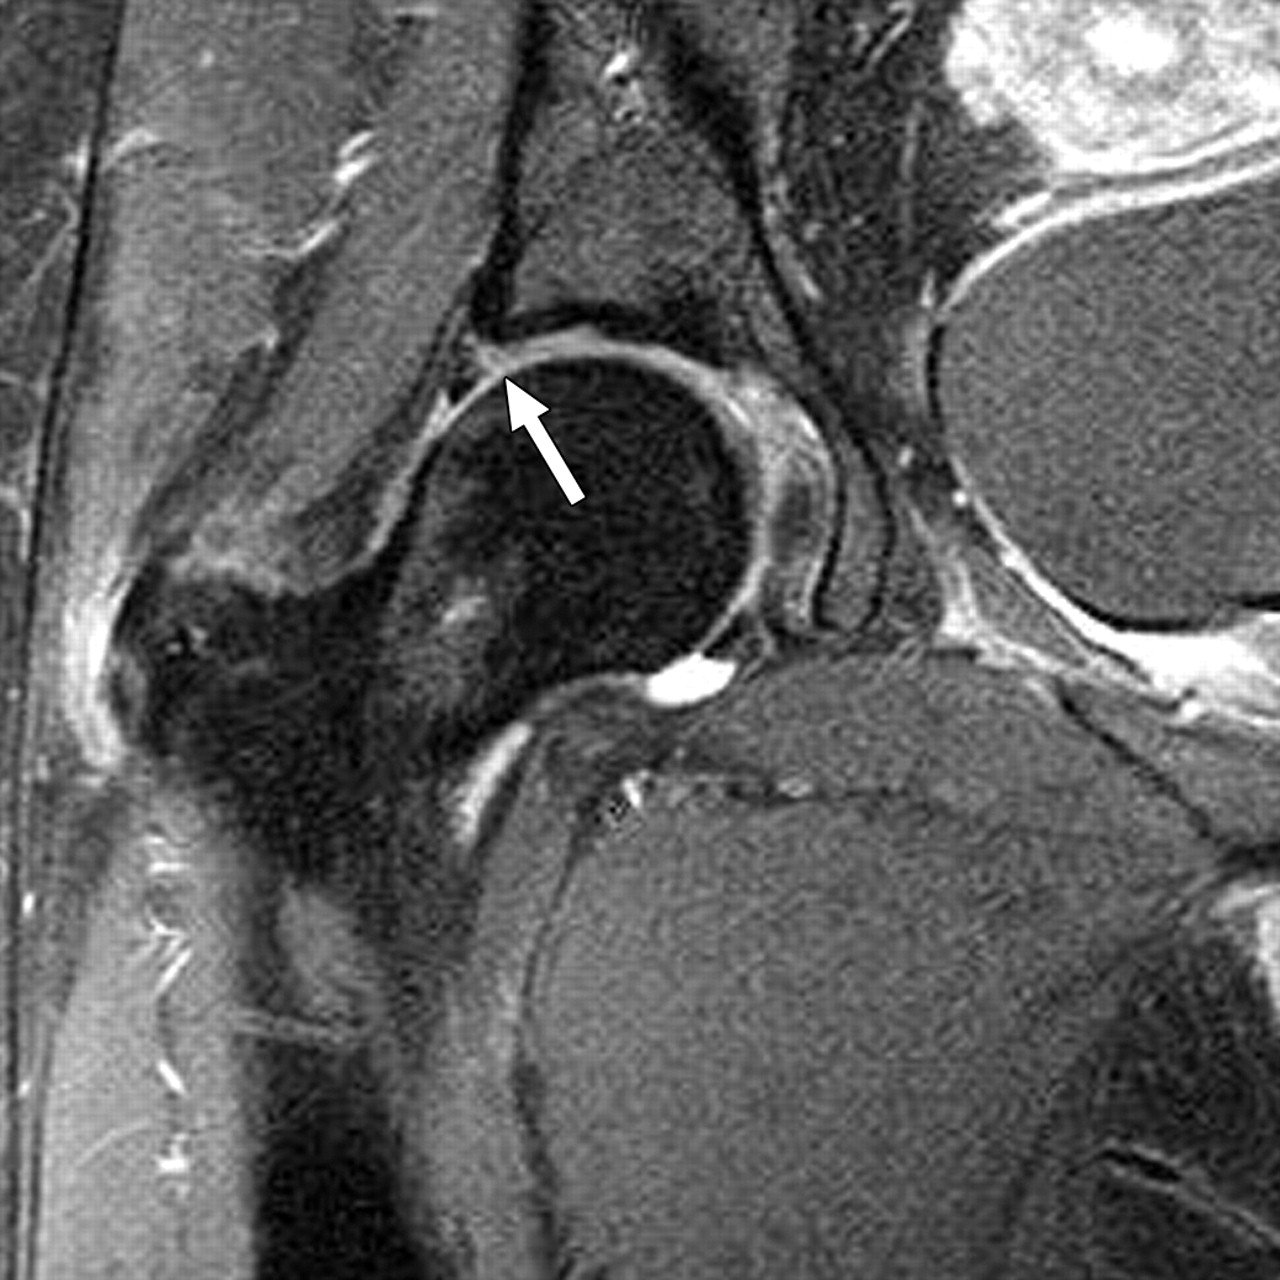

• MRI or MR Arthrogram: Imaging with contrast dye provides detailed visualization of labral integrity and any cartilage injury.

MRI image of a hip labral tear

MRI of a hip labral tear